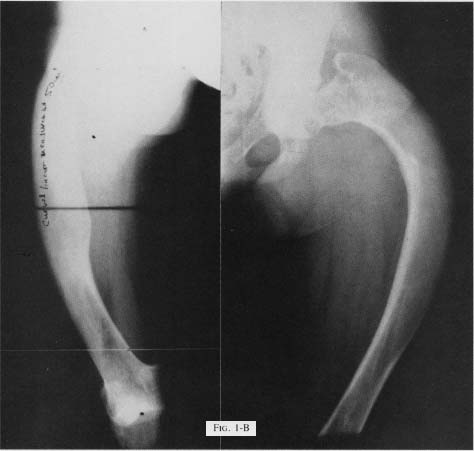

Figure 1 B - Rt femur - s/p 5 fractures treated closed. Lt femur - s/pfailed corrective osteotomy